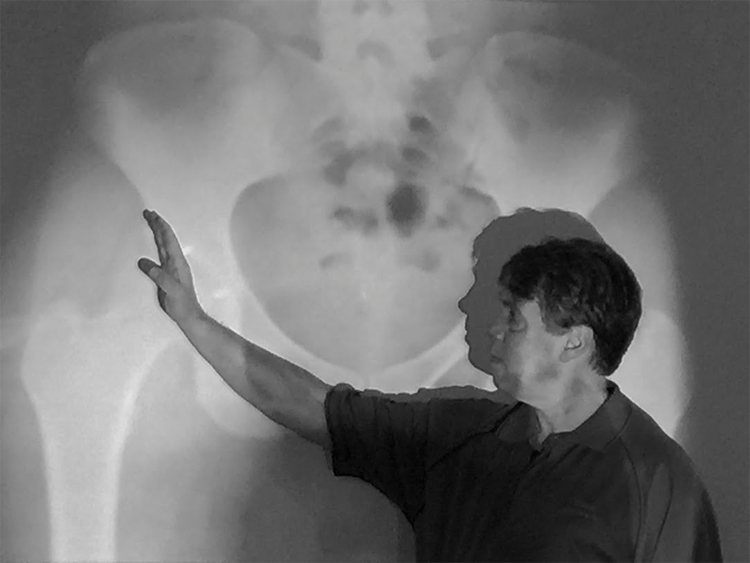

Today begins with a 6:30 breakfast meeting and a brief outline of the charity’s history from Dr. Powell – now on his 9th mission to Ecuador – a few missions were with another group before the charity was initiated. He makes special note of one reason he was drawn to service the poor in Ecuador: there is a selection of the population, aged 18-32 (85-95% young women) who have significantly progressed high riding hip dysplasia and, sadly, these individuals become extremely socially disadvantaged at having to deal with the condition. They live with pain, may need to walk with a cane at a very young age, usually cannot work, and often, become outcasts in their community.